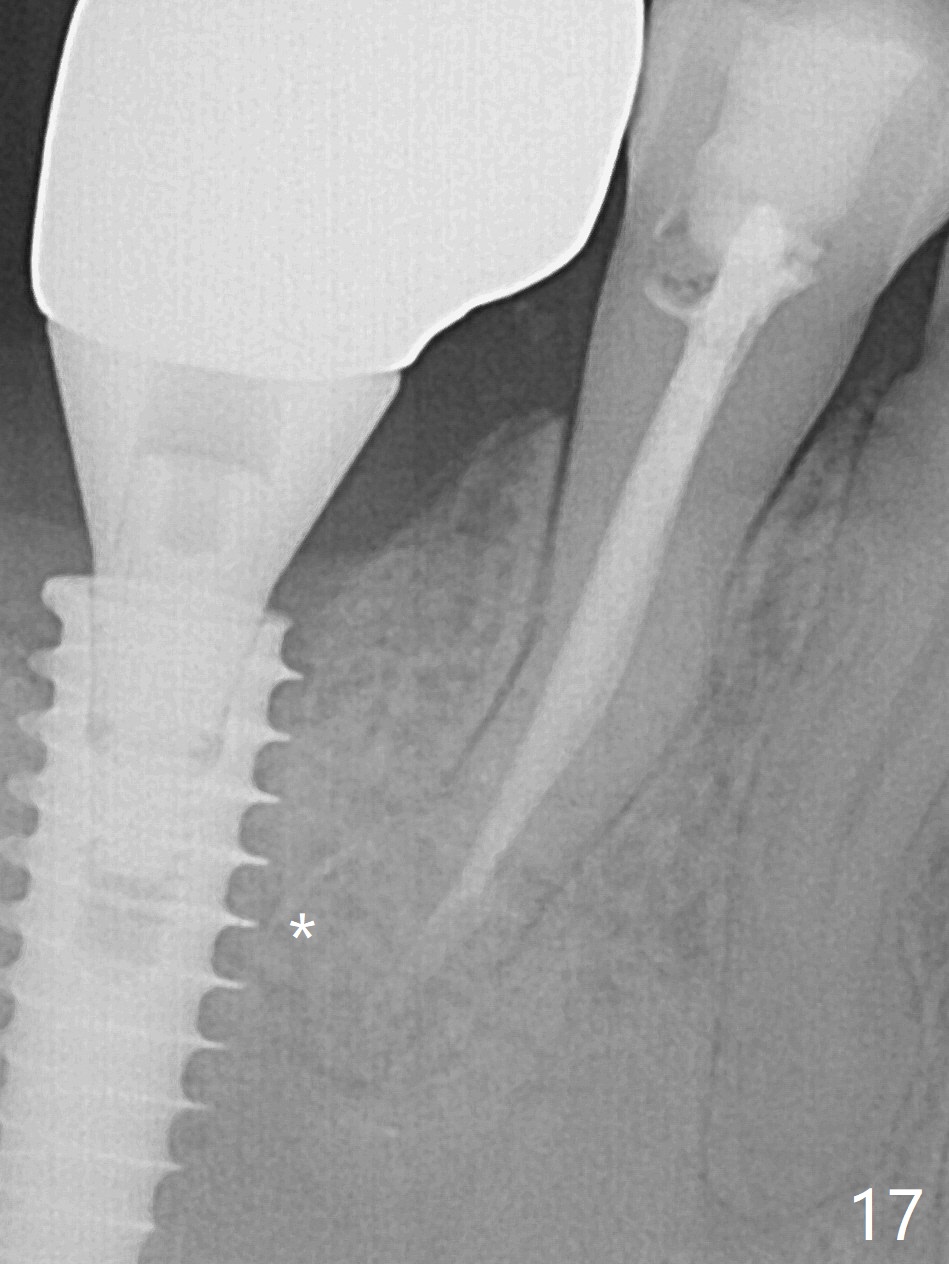

Bone graft seems to sink down and becomes denser 3 months postop (Fig.6 arrow). The bone continues being denser 5 months postop (Fig.7). There is periapical radiolucency of the tooth #29 (^). RCT is done (Fig.8). The pain persists 2 weeks postop (Fig.9,10). There is no missing canal (Fig.9). The apex is close to the implant (Fig.9 *). Apicoectomy will be performed if needed. It appears that the implant is also placed buccal (Fig.10 <) and/or the implant too large for the site. Therefore there should be a 2-3 mm buccal gap before and after implant placement. Separation and reflection of the buccal flap allows better visibility. The pain persists 1 month post RCT and 6 months post implant placement. RCT retreatment is initiated (Fig.11,12) with placement of Calcium Hydroxide paste after redebridement with 30/.04 rotary file at 23.5 mm (.5 mm longer than the earlier RCT, Fig.13). RCT retreatment finishes with apparent transportation and extrusion in 4 weeks (Fig.14,15), followed by apicoetomy (Fig.16,17) (20 days later)). Discomfort remains 2.5 months postop (Fig.18). Keep watching.